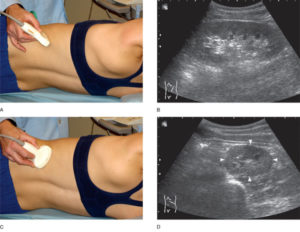

- исследование проводят в положении больного на боку и спине для максимального улучшения качества и увеличения области визуализации;

Пациент при процедуре находится в нескольких положениях: горизонтально – на спине и на боку, вертикально и сидя. На предварительно освобожденную от одежды кожу наносится специальный гель для улучшения распространения ультразвуковых волн.

Обследование почек и мочевыделительной системы проводится в нескольких позициях: лежа, на боку, стоя или сидя. На кожу пациента врач-сонолог наносит гипоаллергенный гель на водной основе, чтобы обеспечить наиболее полный контакт датчика с поверхностью тела пациента и повысить уровень передачи ультразвуковых волн.

Сначала исследуют почки в продольном направлении (поясничная область), затем изучают поперечные и косые срезы, перемещая датчик на переднюю и боковые поверхности живота.

При этом пациента просят поочередно повернуться на правый и левый бок.

Такая техника позволяет определить локализацию (месторасположение) почек, их размеры и форму, оценить состояние паренхимы, почечных синусов, чашечек и лоханок.

Для определения подвижности почек и улучшения визуализации органов при каждом изменении положения тела врач просит больного вдохнуть и на несколько секунд задержать дыхание. На вдохе почки опускаются из-под реберной дуги и просматриваются намного лучше. Узи почек стоя делают при подозрении на нефроптоз (опущение одной или обеих почек).